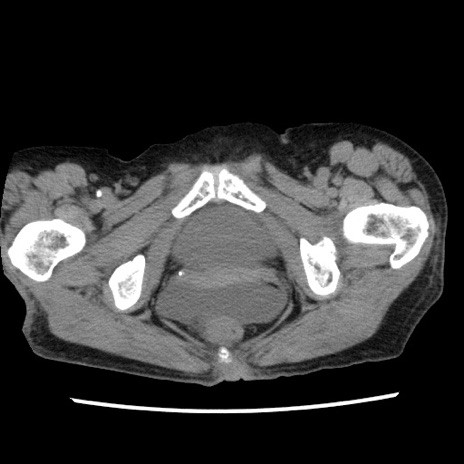

症例1(横断像)

【症例】80歳代女性

【主訴】腹痛

【現病歴】8時間前から腹痛あり来院。

【既往歴】糖尿病、脂質異常症、子宮体癌にて子宮全摘術

【身体所見】意識清明・会話良好だが腹痛で苦悶様、全腹部にわたって反跳痛と圧痛あり

【データ】WBC 13600、CRP 0.14、LDH 224、CK 90